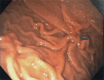

We report the first pediatric use of a laparoscopic-assisted endoscopic overstitch technique for managing an acutely perforated gastric ulcer in a 16-year-old female. The patient presented with symptoms consistent with gastrointestinal perforation, confirmed by radiologic pneumoperitoneum. Diagnostic laparoscopy identified inflammatory adhesions and a gastric ulcer perforation. Concurrent endoscopy precisely located the defect, which was effectively closed using an endoscopic overstitch device mounted on a therapeutic double-channel gastroscope. Closure involved three full-thickness inverted figure-of-eight sutures, verified by an intraoperative leak test and reinforced with an omental patch. Postoperative recovery was rapid and uncomplicated, progressing to a regular diet within 3 days. This innovative hybrid laparoscopic-endoscopic technique demonstrates efficacy, safety, and the benefits of minimally invasive surgery for pediatric gastrointestinal perforations, emphasizing its potential superiority over traditional methods.